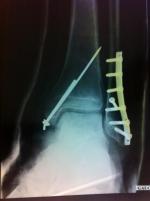

Le retour jusqu'à Grenoble est sacrément rapide. La porte latérale est ouverte, je profite du décor sur Belledonne, le Grésivaudan, Grenoble. On arrivera sous la pluie sur le toit de la Clinique des Cèdres où des demoiselles en blouses blanches prendront gentillement le relais. Et les conclusions des radios seront : fractures bi-malleolaire, pied gauche.

Je serai opéré dans la semaine. Plaque, vis, broches viennent réparer mes péroné et tibia tout fracturés. Le tout platré. Puis après quelques jours au CHU Sud, je poursuivrai à la maison mes journées au lit, la jambe en l'air.

Fractures bi malléolaire